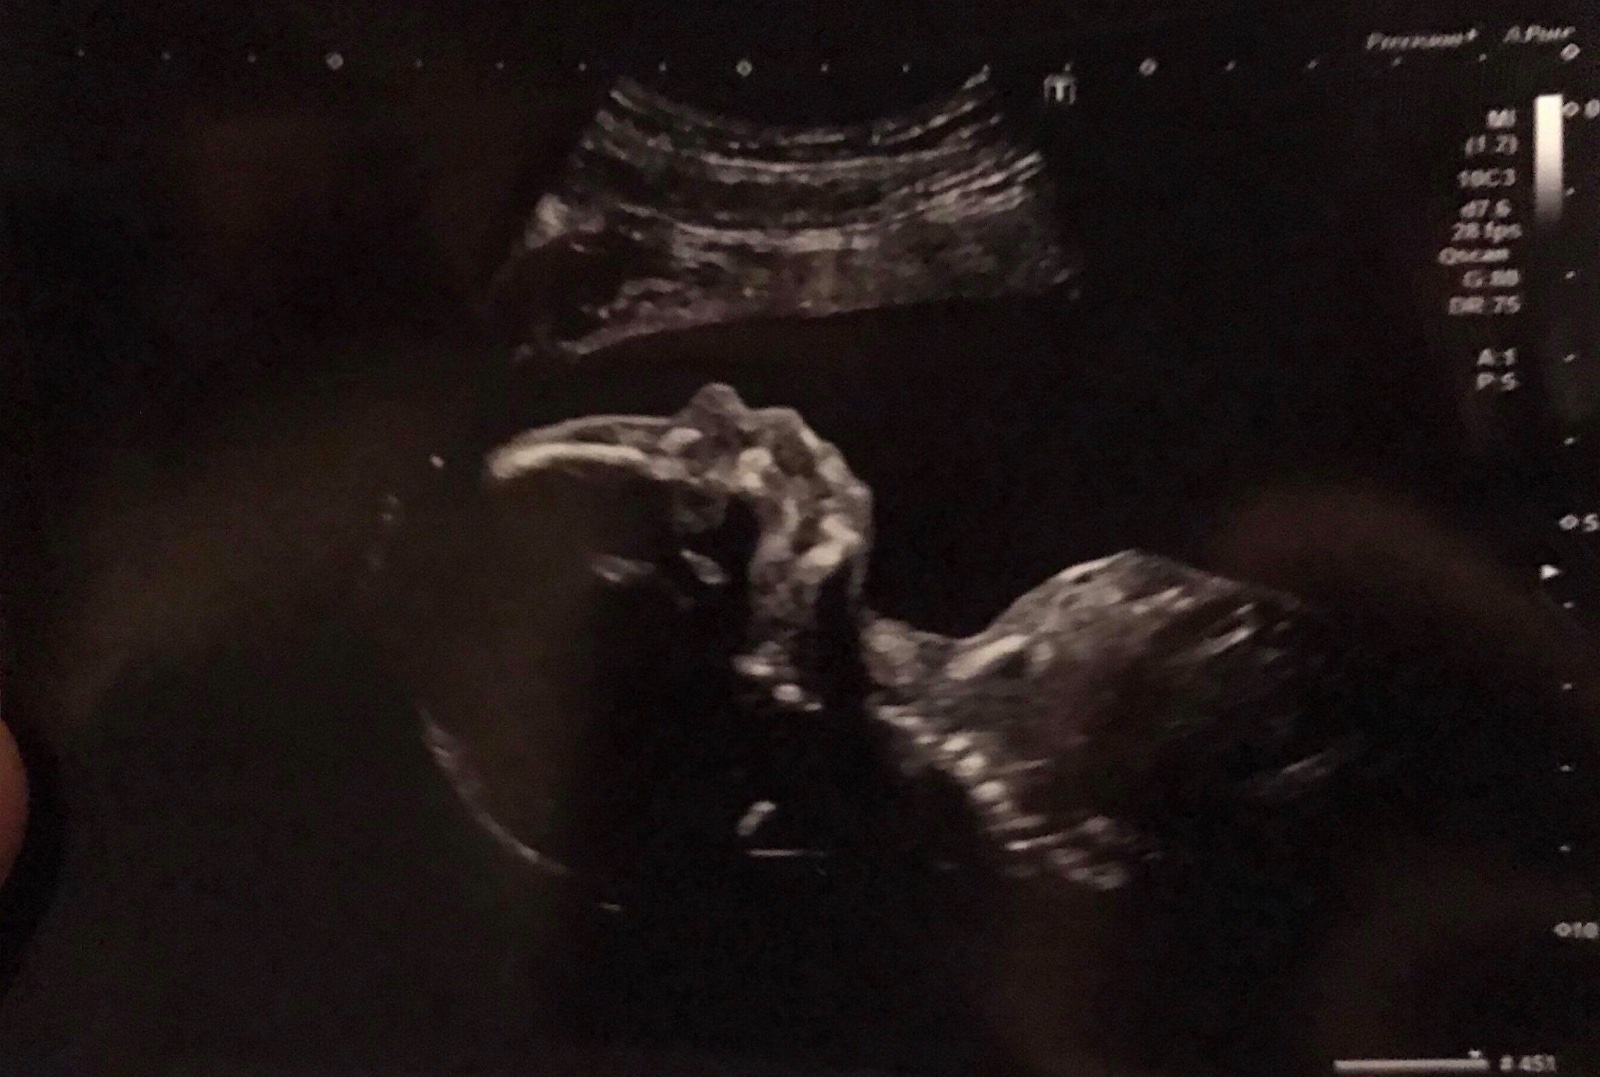

Holky ja se musim porad smat,kdyz vidim fotku mininka : ))), se na ni tvari jako nejvetsi nejklidnejsi andilek, jako “ja nic ja muzikant” a pritom tam delal takovy rosady,ze nesel vubec zmerit : ))), a 4D UTZ jedna velka rozmazana smouha : ))), tak max ruku jsme videl jak nam vehementne maval : ))) ... typickej chlap uz od narozeni no

Jak už jde krásně vidět nosík,pusina,bradička..taky už se těším na ultrazvuk jdu příští týden.

@mattonimeloun jo uz je to proste lidsky tvor, neuveritelny